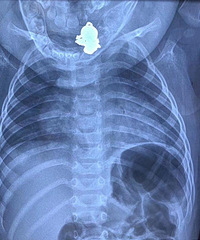

【千万小心!】来自深圳市儿童医院医生的忠告: “千万不要建议黄疸的新生儿去晒太阳…… 新生儿黄疸,虽然很常见,足月儿发生率大概50%,早产儿70%。 但有轻有重,轻者无需治疗,可自愈。重者,数小时内就变成脑病,并且一旦脑病,终身痴呆、瘫痪甚至快速死亡。